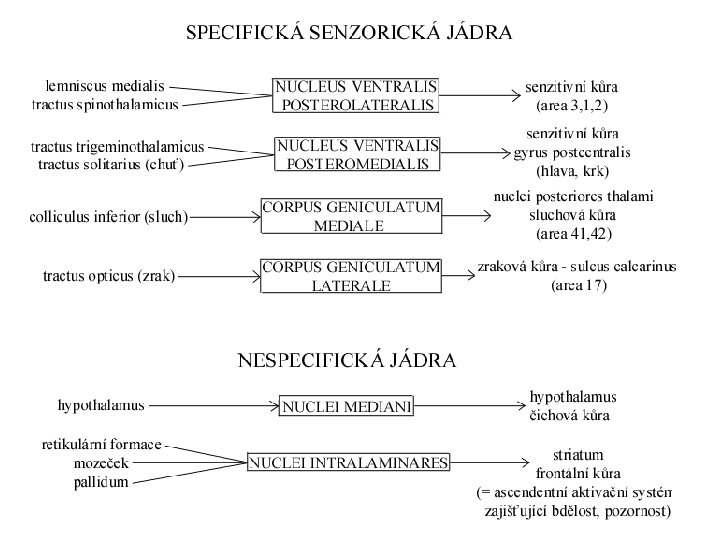

Thalamus (thalamus dorsalis) • • • „sekretářka mozku“ vše kromě čichu pulvinar (dorzálně) tuberculum anterius (ventrálně) lamina medullaris medialis + lateralis thalami adhesio interthalamica (80 %) – bez významu jádra se rozdělují se podle polohy nebo zapojení – nuclei anteriores, dorsales, intralaminares, mediani, mediales, posteriores, ventrales, reticularis – specifická senzorická jádra – specifická nesenzorická jádra – nespecifická jádra – asociační jádra

Třídění thalamických jader dle polohy nuclei anteriores, dorsales, intralaminares, mediani, mediales, posteriores, ventrales, reticularis

Specifická jádra • tractus mamillothalamicus ncl. anterior gyrus cinguli – opakované kroužení zesiluje emoce • globus pallidus ncl. VA prefrontální kůra • globus pallidus ncl. VL doplňková motorická kůra • nucleus dentatus cerebelli ncl. VL motorická kůra • lemniscus medialis et spinalis ncl. VPL senzitivní kůra • lemniscus trigeminalis ncl. VPM senzitivní kůra

Asociační jádra • ncl. LD (lat. dors. ) area cingularis posterior • čichový a limbický mozek ncl. MD (mediodors. ) prefrontální kůra (myšlení, úsudek, nálada, stav mysli – integrace se smyslovými podněty) • colliculus superior ncl. LP (lat. post. ) + pulvinar zraková a parietální asociační kůra (přitahuje pozornost k objektům v periferii zrakového pole) • ncll. P (pulvinar) frontální, temporální, parietální a okcipitální asociační kůra (integrace zrakových, sluchových, hmatových a polohových podnětů)

Nespecifická jádra • ncll. intralaminares – pomalá bolest – ARAS • ncll. mediani • limbický systém (dle eferentace)

Metathalamus • corpus geniculatum laterale – centrum zraku • corpus geniculatum mediale – centrum sluchu